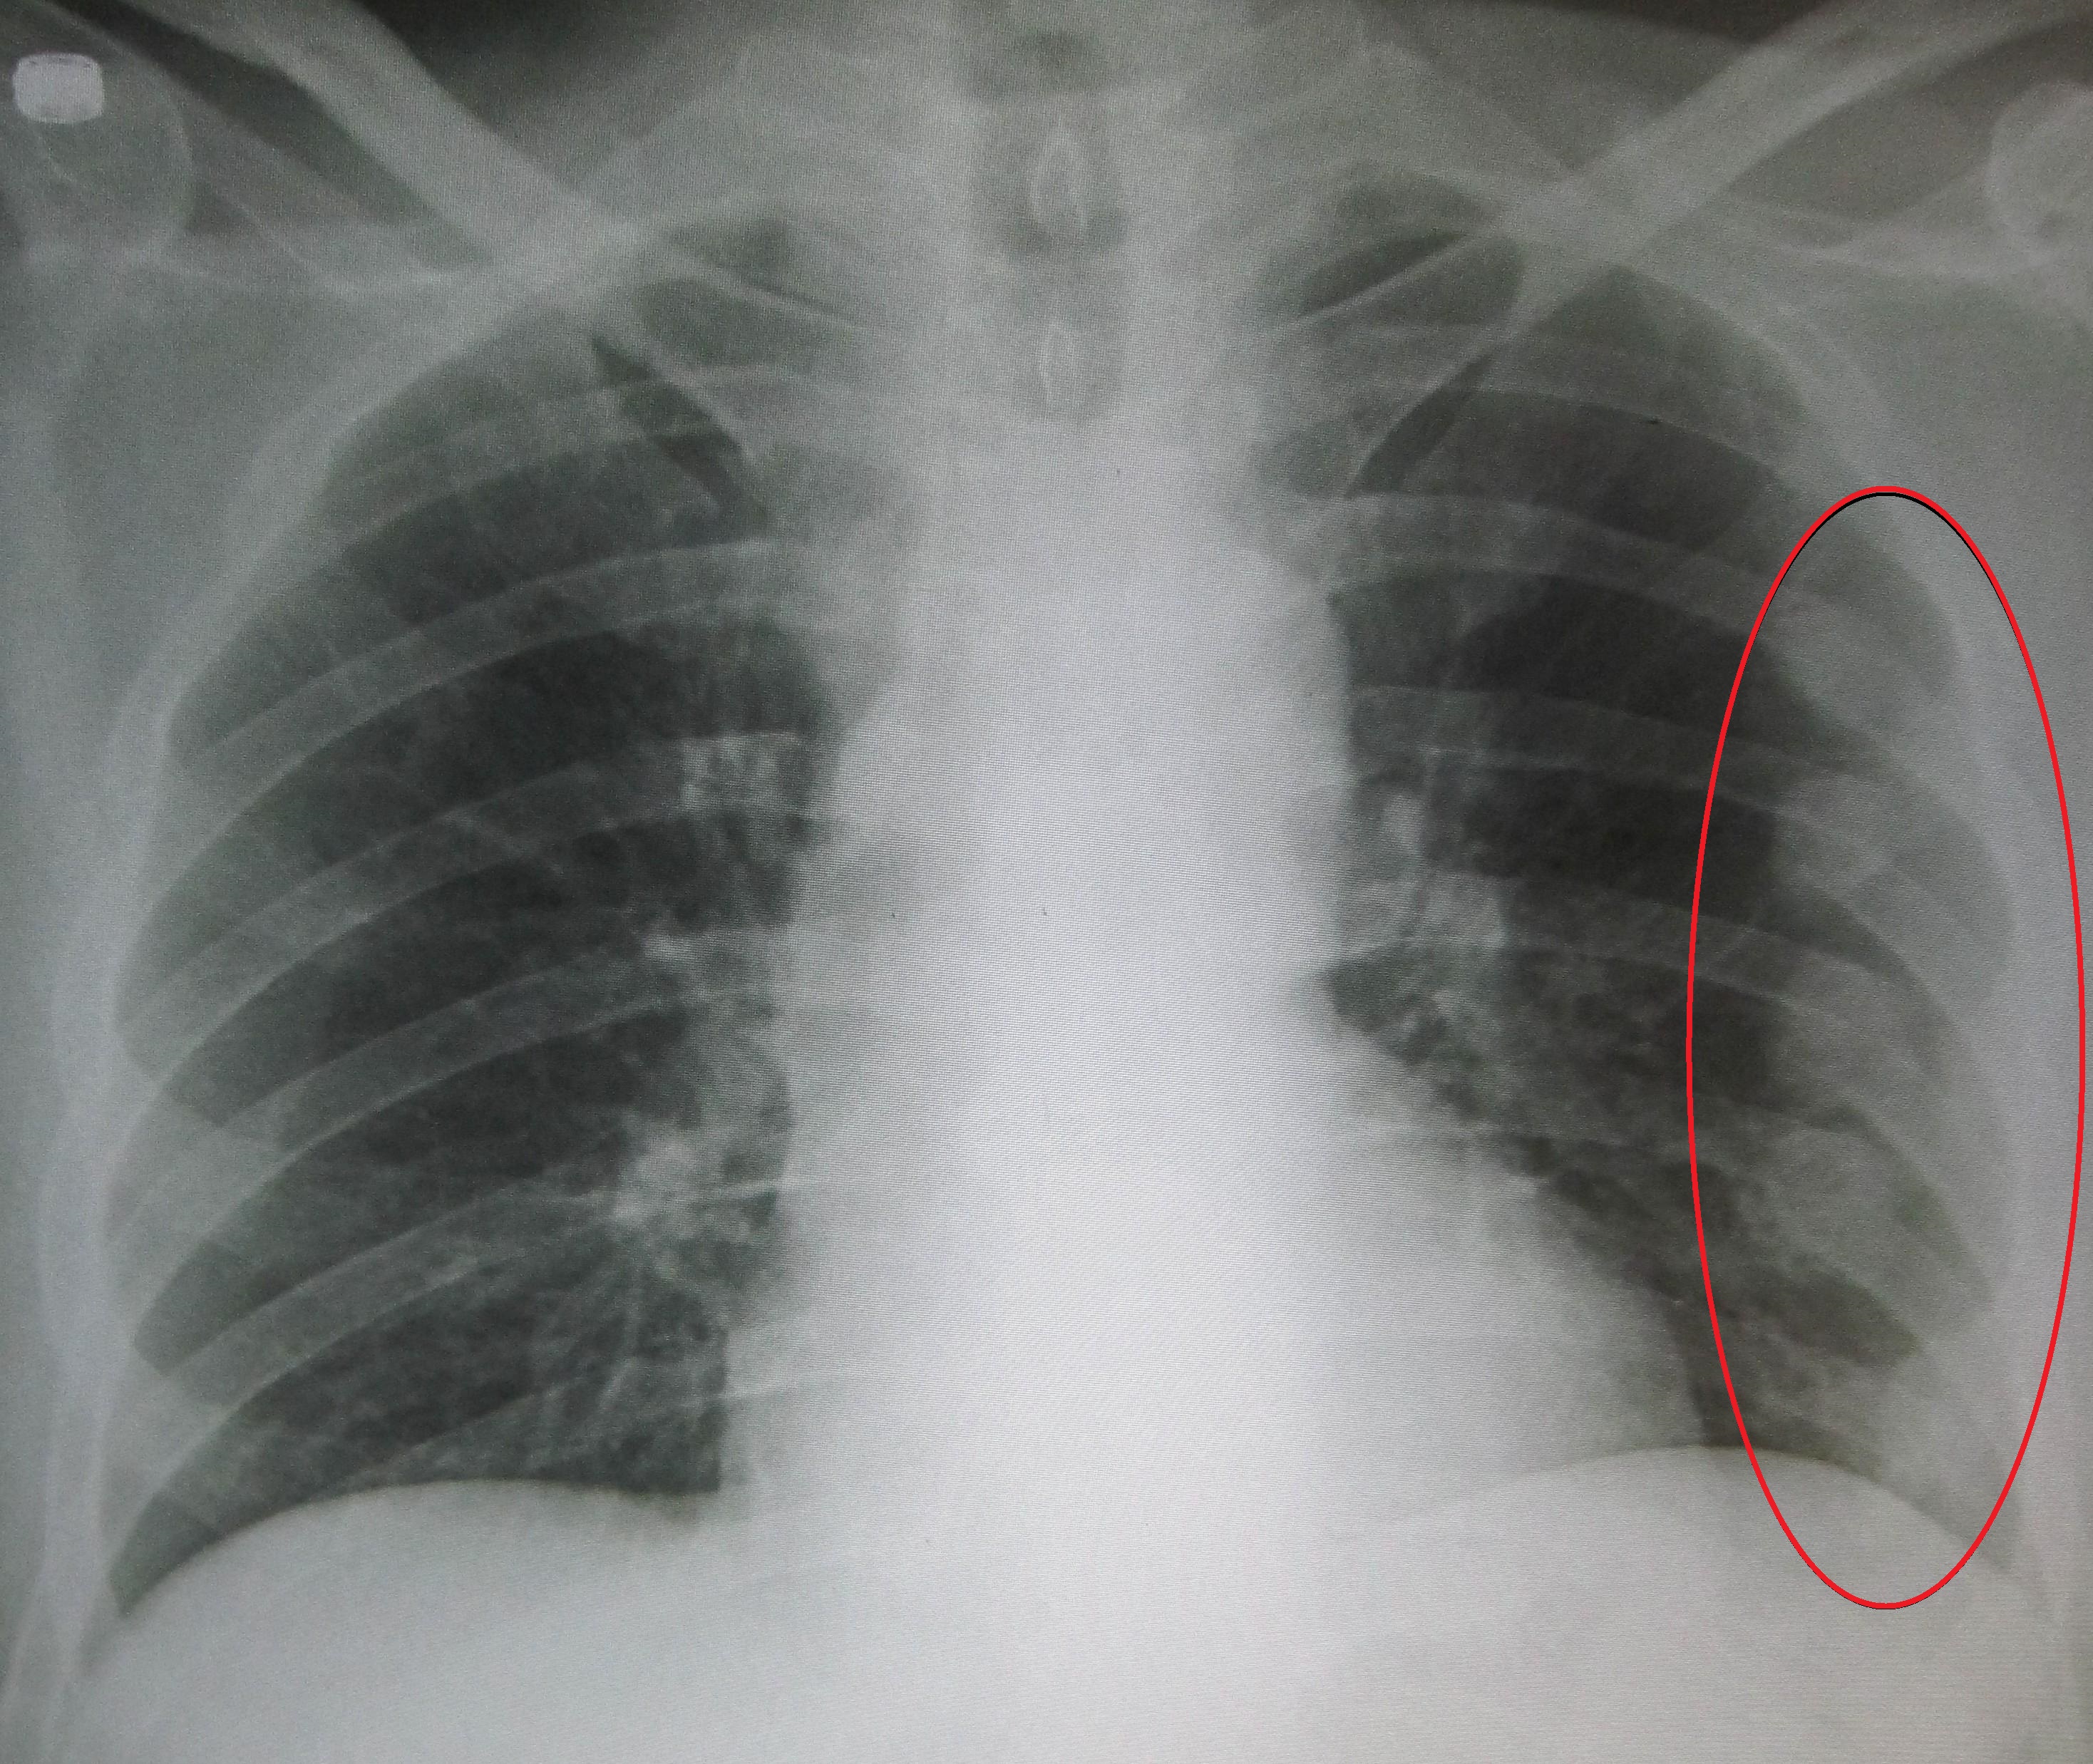

An X ray showing multiple old fractured ribs of the persons left side as marked by the oval, James Heilman, Wikimedia Commons - https://commons.wikimedia.org/wiki/File:Fracturedribsmarked.jpg

Eleven per cent of 407 patients in NZ with broken ribs caught pneumonia, finds the first study to look at rib fracture management and outcomes in multiple New Zealand hospitals. In addition to the pneumonia cases, the study found two per cent of rib fracture patients died. The NZ pneumonia rate is higher than some overseas reports, with a large US study finding theirs was just two per cent. Furthermore, eight per cent of patients were admitted more than once for rib fractures, with Māori and older people over-represented. The authors say NZ’s pneumonia rate among people who've broken their ribs could be lowered with quality improvement initiatives, and the repeat fractures in Māori and older people should be investigated.